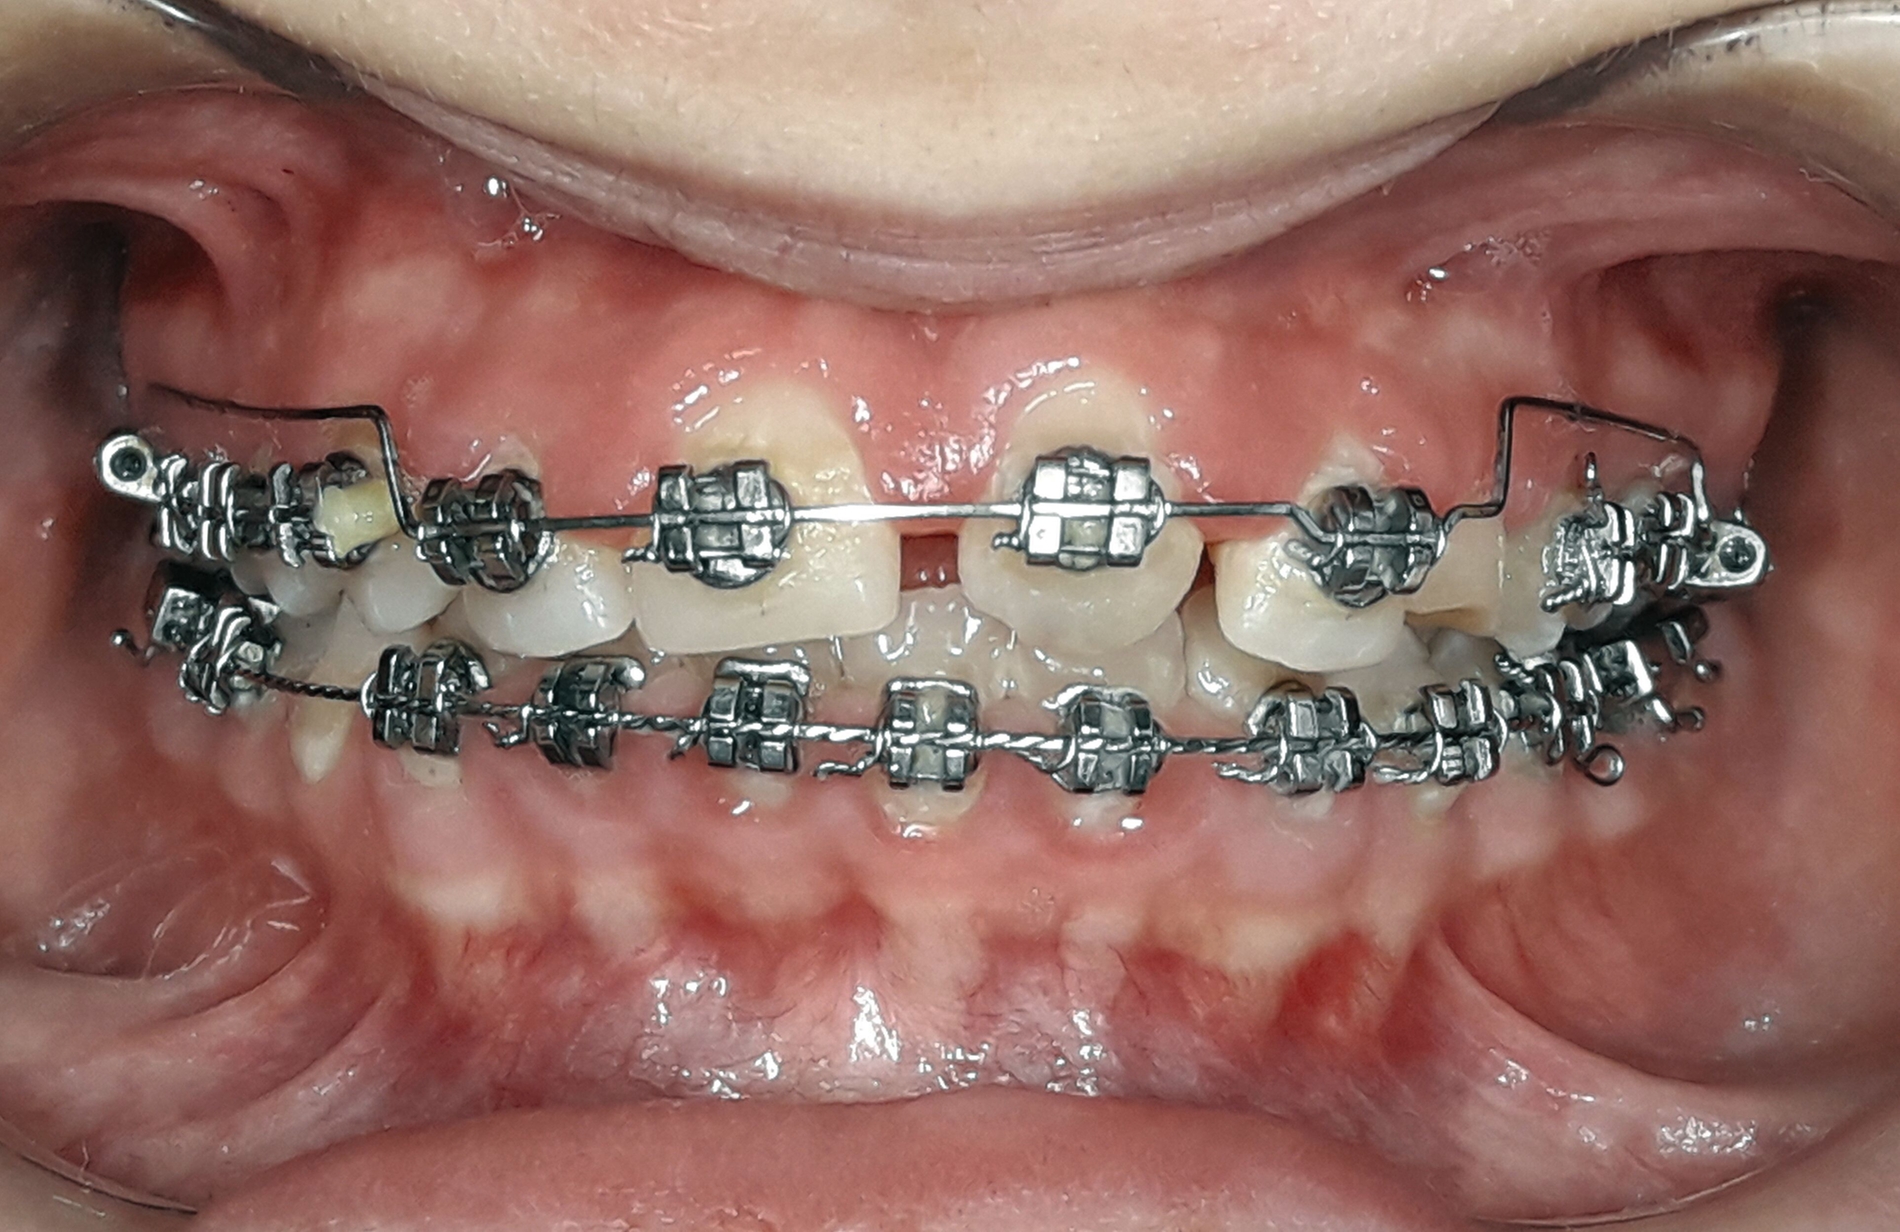

Die visuelle Beurteilung der Lage der Schneidezähne ergab, dass die Lippenlinie sehr niedrig war und diePatientin eine konkave Lachlinie aufwies. Deshalb wurde die „2 x 4-Segmentbogentechnik“ angewendet, um die Oberkieferfrontzähne zu extrudieren, die Exposition der Oberkieferschneidezähne zu erhöhen und die Lachlinie zu nivellieren (Abbildung 6).